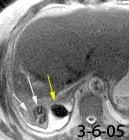

Hallazgos en RM .

Buena en casos dudosos

Cortes sagitales y coronales: Interrupción de la línea diafragmática

Paciente que ingresa con síntomas de colecistitis aguda. Antecedentes de trauma importante muchos años antes

Zhao L et al. Delayed traumatic diaphragmatic rupture: diagnosis and surgical treatment. © Journal of Thoracic Disease.

J Thorac Dis 2021

Asas

Líquido pericolecistítico

V. biliar con cálculos

Diafragma